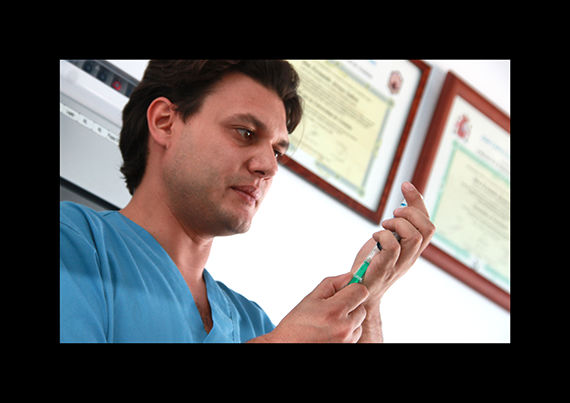

vacunaciones

La prevención de la las enfermedades a través de la vacunación es la mejor manera de que nuestro animal no sufra enfermedades que hagan peligrar su vida por eso en clinican le ofrecemos vacunas de gran calidad